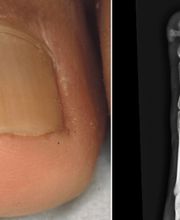

Il medico specialista Dr. Pier Alessandro Fanti opera nel settore della dermatologia e anatomia patologica, il dottore oltre a queste specializzazioni si occupa anche di malattie veneree. Il medico specialista Dr. Pier Alessandro Fanti è il dirigente medico dell'unità operativa dermatologia del Policlinico Sant'Orsola Malpighi. Il dermatologo presta la massima attenzione ai suoi pazienti garantendo esperienza nel settore e ladeguata competenza nella soluzione di problematiche e patologie varie. Il Dr. Fanti si occupa di patologia annessi cutanei, chirurgia microscopicamente controllata, dermatologia oncologica, ma anche di terapie e trattamenti per la chirurgia unità ungueale, crioterapia e trattamenti laser CO2.